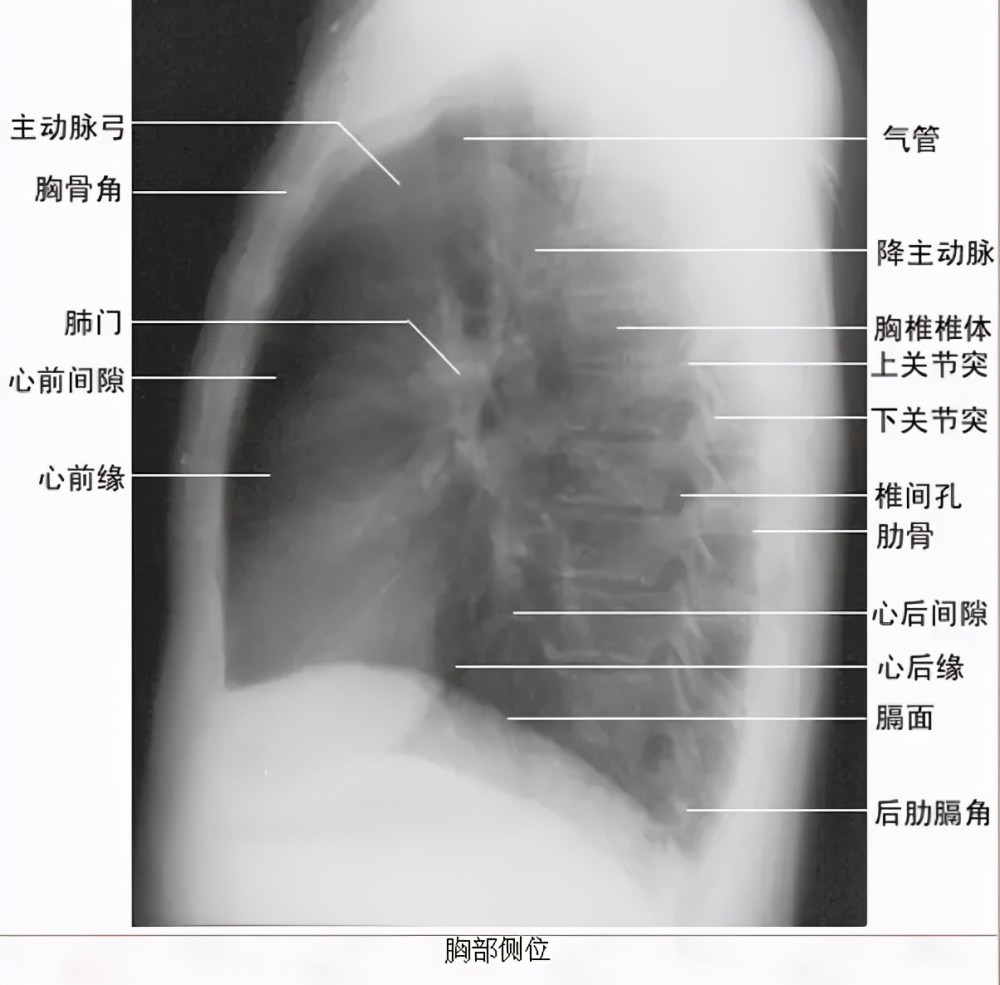

胸部侧位片上图为正常胸部后前位片临床拍标准的胸部正位片其实是